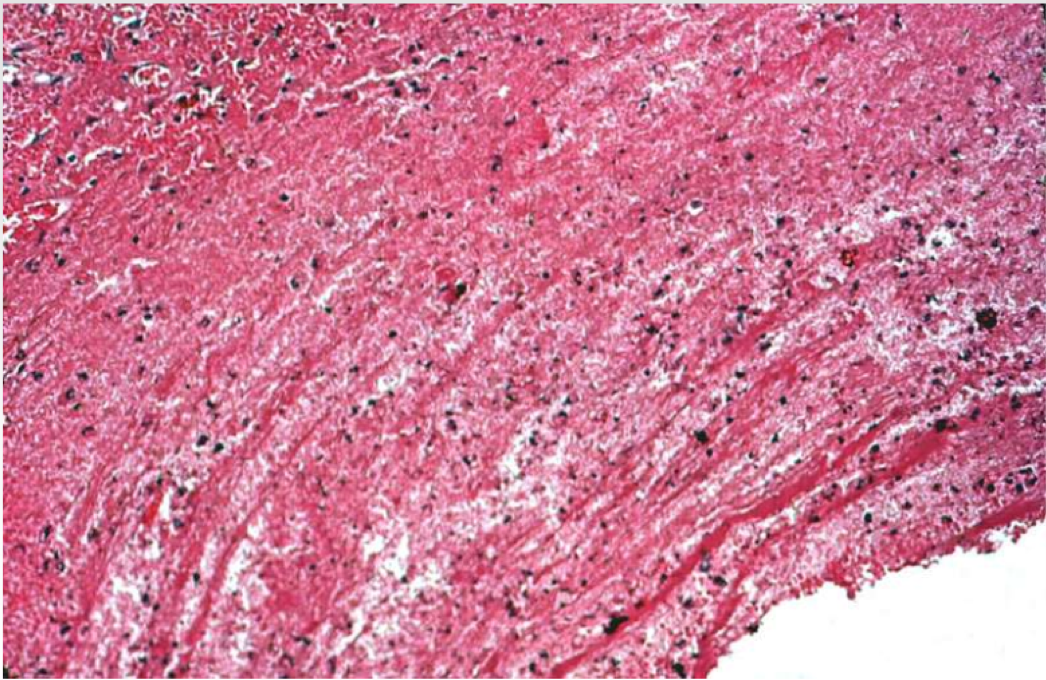

What can be seen in this thrombus?

Lines of Zahn